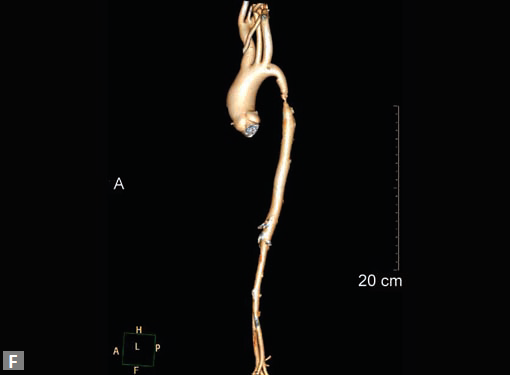

Rarely complex heterotaxy (Figs 19D to F) syndromes present

as pulmonary hypertension.

Figs 19A to Y (A to C) Scannogram (A), plain (B) and contrast study (C) show partial anomalous pulmonary venous connection; (D to F) Heterotaxy; (G) Aortic occlusion; (H and I) Aortic stents; (J) Aortic dissection with ‘Benz’ sign due to second dissection within the true lumen; (K, L and M) Aortic dissection with thrombus in pseudolumen following catheter angiogram; (N) Aortic dissection involving common carotid arteries and subclavian artery; (O, P, Q and R) Aortic dissection with right renal artery arising from true lumen and left renal artery from false lumen; (S, T, U and V) Stanford B dissection with extension Y to iliac vessels; (W to Y) Aneurysmal dilation of ascending aorta